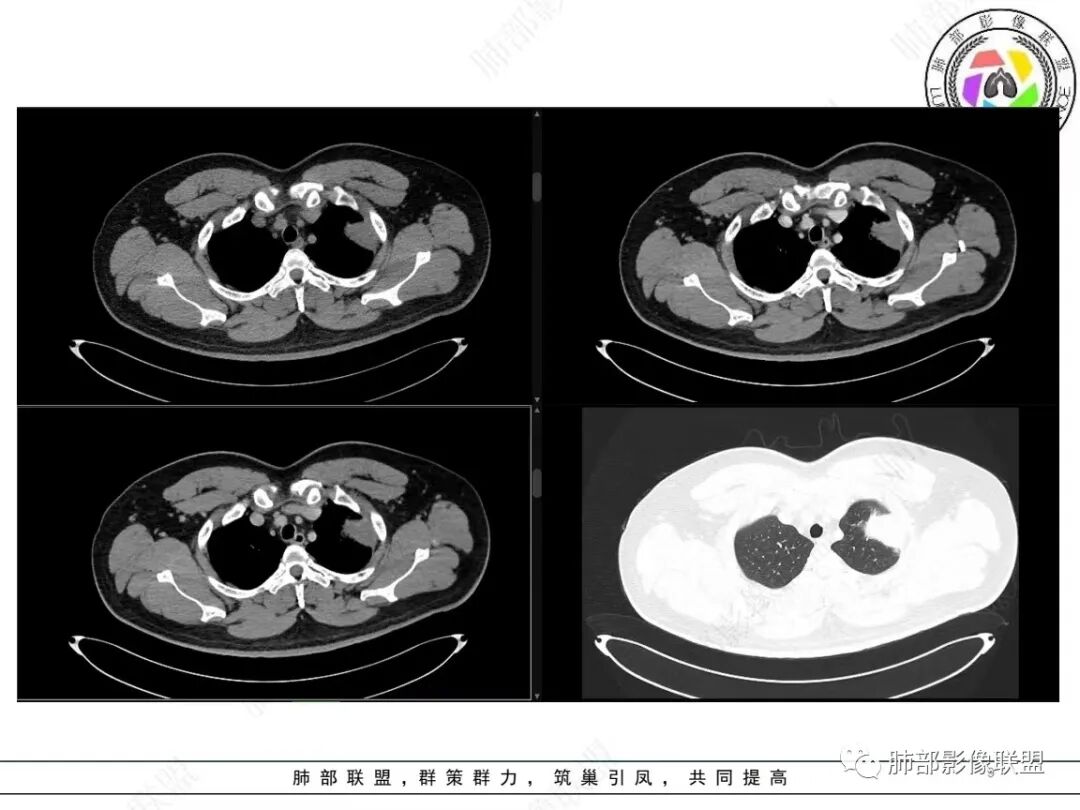

青年男性,咯血;CT示左肺上叶胸膜下软组织肿块,边界尚清,宽基底与胸膜相连,增强动脉期内见细条状血管影,轻度延迟强化,定位:肺外,胸膜外脂肪存在,考虑脏层胸膜起源;定性:考虑SFT。

影像表现:左肺上叶占位合并出血,胸膜栽赃,边缘强化,局部见血管影,中心密度20Hu,无强化,符合非液化坏死。定位:肺内,定性恶性(明显血管影,栽赃排除错构瘤,中心无强化排除PSP,无明显清楚的坏死边界,强化不符合肉芽肿,排除结核),年龄轻,无长时间吸烟史和肺气肿改变,肉瘤样癌可能性很小,与支气管无确切关系,所以病理类型考虑来源于肺间叶组织的肉瘤,骨外尤文?滑膜肉瘤?

有血供,强化不明显,周围肺出血,肺组织受压改变,定位肺外,胸膜增厚,部分胸膜下脂肪间隙存在,不确定肋骨是否受侵犯,部分层面与肺动脉分界不清,感觉推移,如果供血要考虑sft,强化不符合,有血管进入,但是强化不明显,密度相对均匀,所以不考虑坏死,富含粘液可能,咯血,说明累及支气管了,有一定侵袭性,肿块大,考虑间叶来源肿瘤,与胸膜接触面相对不是宽基底,综合考虑滑膜肉瘤可能,典型的滑膜肉瘤一般铺路石改变,这个又觉得信号相对均匀了一些学习中

定位肺内明确,来源间叶组织明确,年龄和吸烟史情况排除肉瘤样癌,剩下的就基本上只有骨外尤文和滑膜肉瘤了,再加上强化低,骨外尤文就肯定首先考虑。